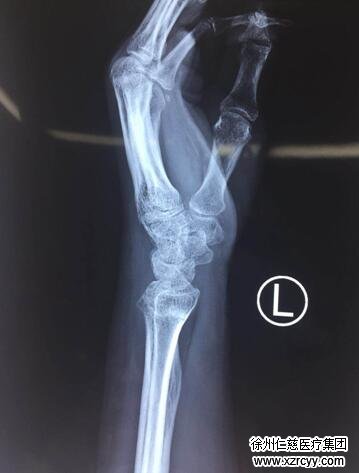

李大妈不敢再拖了,赶紧来必威官方首页官网betway挂了手外科的号。值班的手外三尚卫国医生接待了她。听李大妈诉说了病情,尚医生给她进行了细致的检查,发现李大妈的左手腕部有些肿胀,拇指不能主动背伸,被动背伸及主动曲屈功能还比较良好,腕关节活动部分受限,诊断为左手拇长伸肌腱断裂。拍片发现桡骨远端不平整,考虑是陈旧性桡骨骨折,一问,李大妈才想起,一年前,她也摔过一跤,也是左手撑地,疼肿了几天,没上医院检查,贴点膏药了事,没想到这一摔竟摔骨折了。

尚医生告诉李大妈,老人摔跤别不当回事。就是这个一年前她没在意的骨折,“磨断”了她的拇长伸肌腱。因为一年前的骨折老人没有去医院治疗,自行愈合得不平整,骨折部位翘起来了,此后反复摩擦拇长伸肌腱,才在拧毛巾这一动作的诱因下,导致拇长伸肌腱突然断裂。

第二天,尚医生就给李大妈安排手术。手术中发现,李大妈的拇长伸肌腱已经完全断裂,断端磨损得非常严重,无法进行直接吻合,去掉无法使用的肌腱以后,缺损大概有4厘米,尚医生在老人手腕掌侧做一切口,截取约6厘米长的掌长肌腱进行移植,修补缺损的拇长伸肌腱。